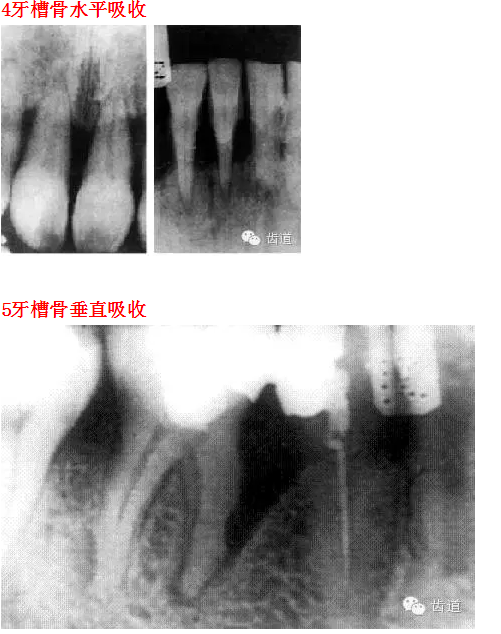

26種口腔病變X光片